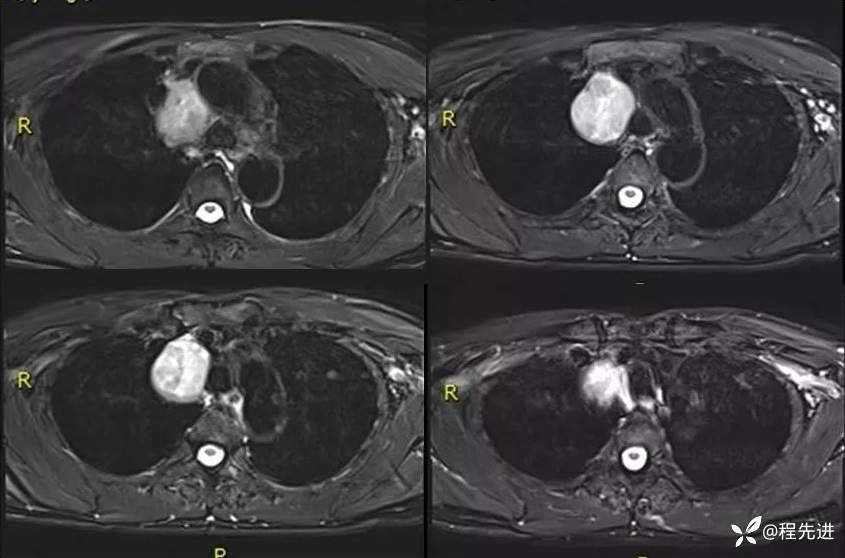

MRI平扫+增强:

T2压脂: